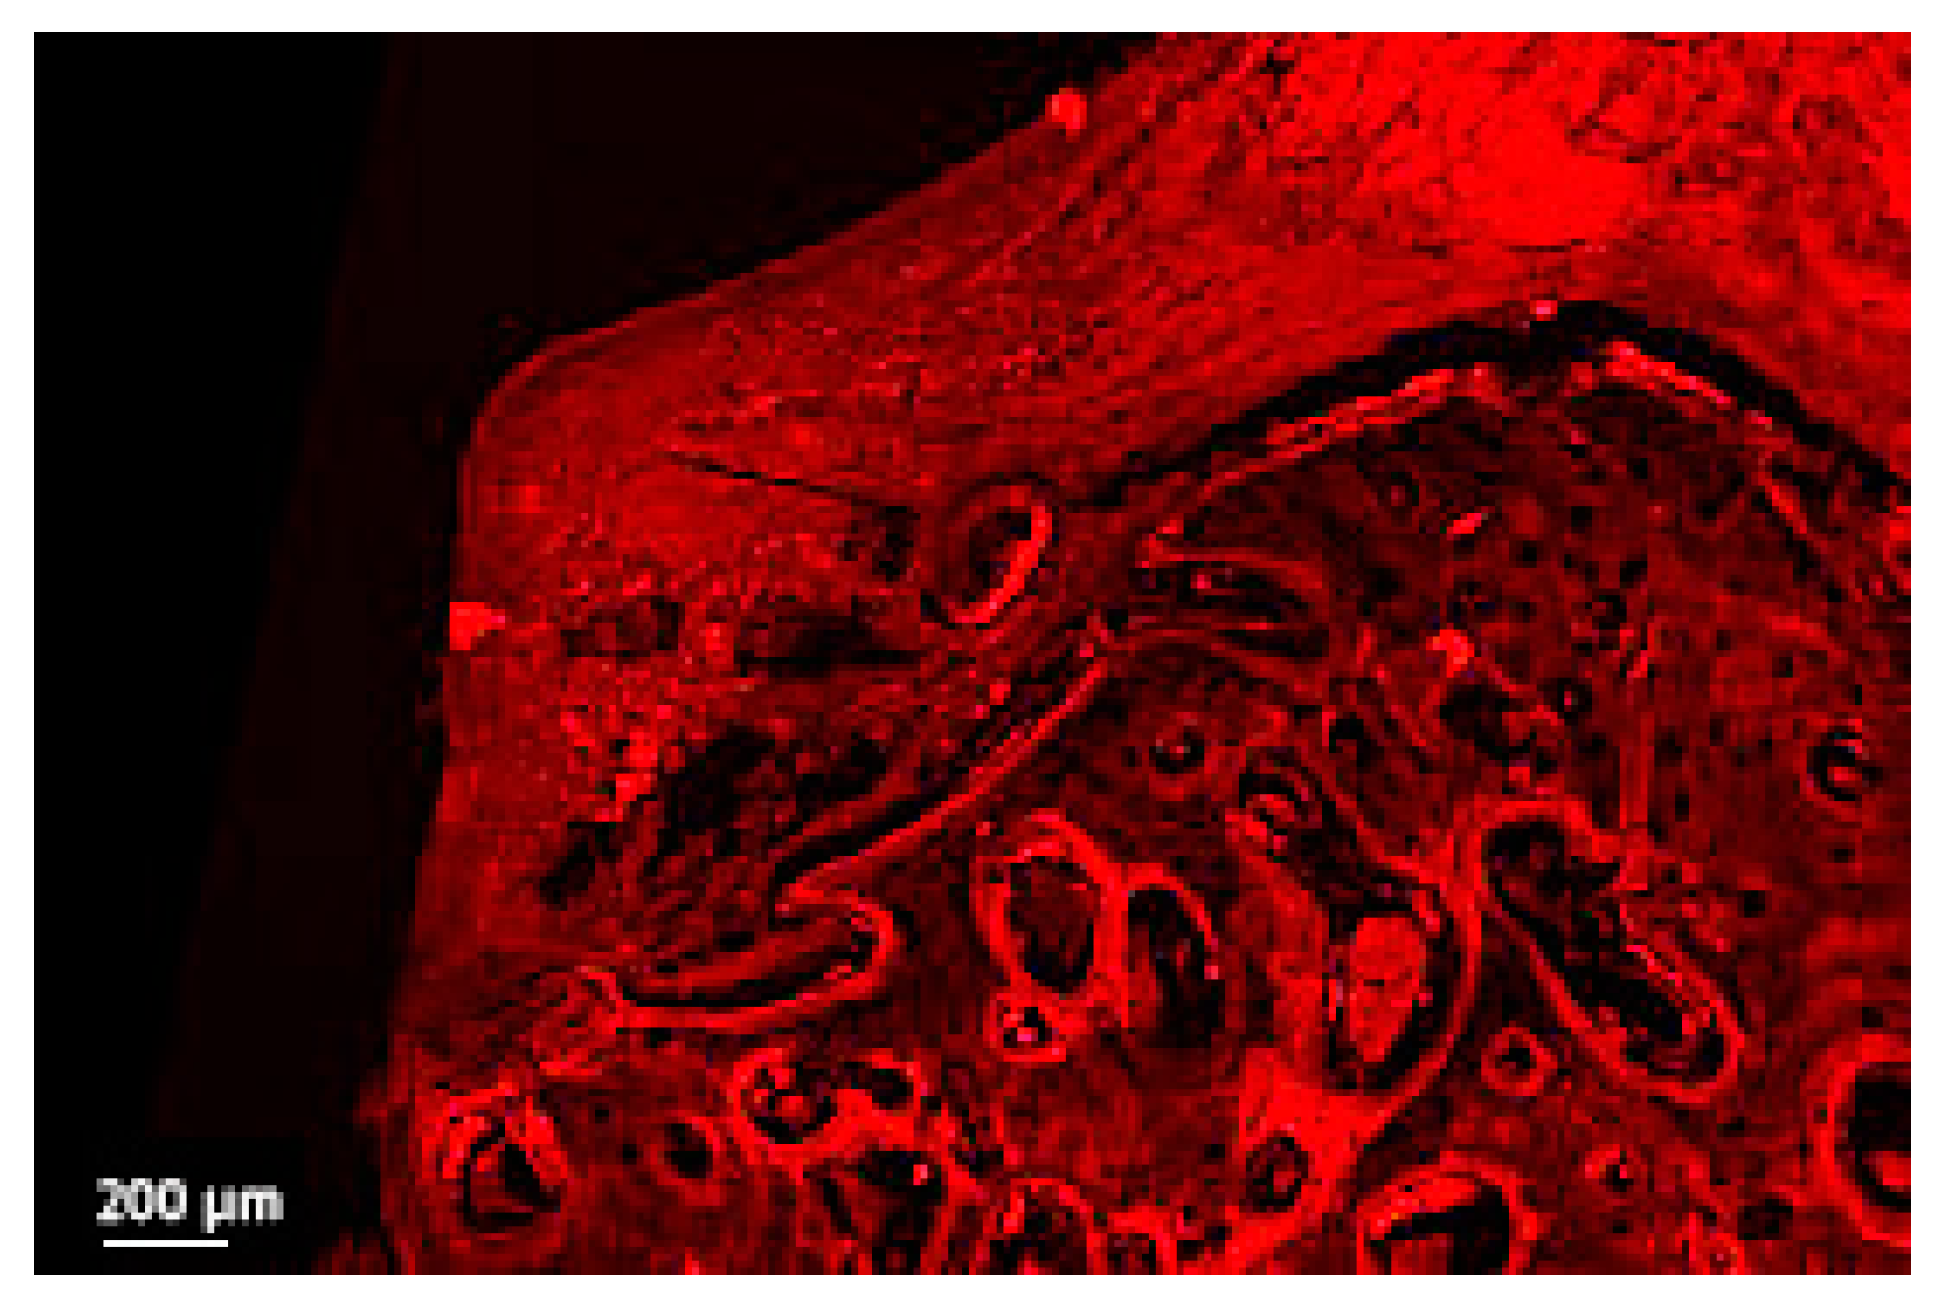

3.1.1. Qualitative Comparison between the Light Microscopy, CLSM Thin, and CLSM Thick Sections

3.1.2. 3D Reconstruction Analysis